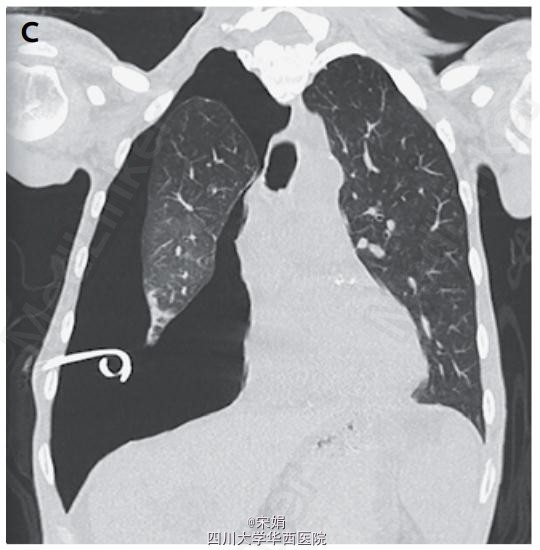

胸部CT扫描发现肺萎陷(伴脏层胸膜增厚,且无气管内梗阻表现(图C)。

此例患者接受了胸腔镜下脏层胸膜剥脱(decortication)及胸膜固定术(pleurodesis),右肺最终完全复张。

肺萎陷是由于慢性炎症过程造成脏层胸膜纤维素性增厚,从而影响肺的复张。顺应性很差的肺与壁层胸膜分离,胸膜腔内充满液体,导致液气胸。由于肺无法复张,因此引流胸腔积液后会导致肺不张后气胸。一旦造成肺不张后气胸的其他病因如气管内梗阻被排除后,可以通过手术治疗肺萎陷,手术去除脏层胸膜纤维素板,以便肺的复张。DOI: 10.1056/NEJMicm1404964